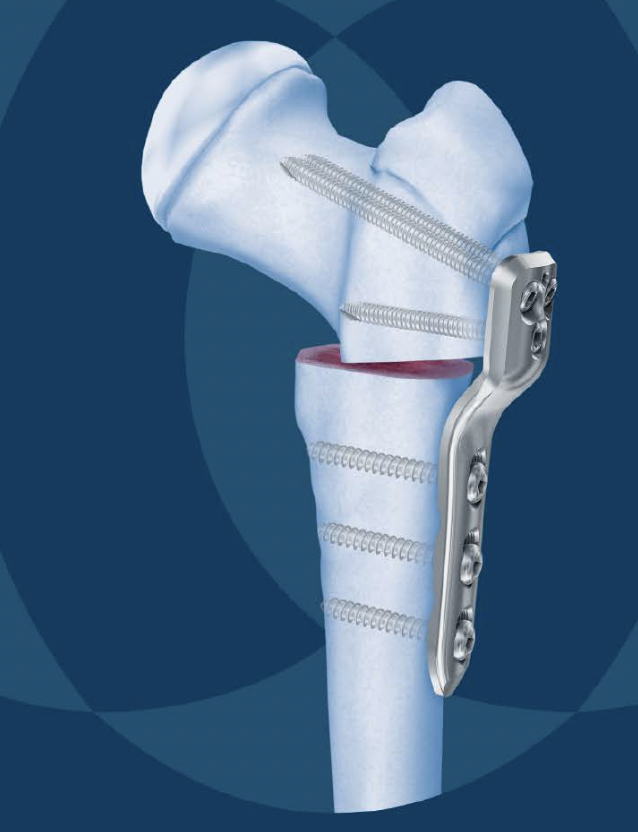

Femoral Varus Derotation Osteotomy (VDRO)

Indication

Tight reduction risking AVN

Unstable reduction with increased femoral anteversion

Increased femoral neck angle

Technique

Synthes Pediatric Proximal Femur Offset Plate Technique PDF

Youtube open reduction and VDRO video

Measure planned correction

- preoperative: 150 degrees

- postoperative: 120 degrees

Separate lateral approach

- elevate vas lateralis +/- release proximally with L shaped release

- open and protect periosteum with Homan retractors

- mark distal and proximal femur with drill holes to check rotation

- place wires up femoral neck short of physis

- use plate to mark osteotomy site

Osteotomy with microsagittal saw 1 cm below lesser tuberosity

- may need to shorten

- +/- adjust version

- apply plate and fix with screws